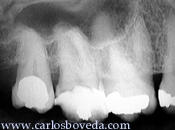

Primer

Molar Superior Derecho

Segundo

Premolar Superior Derecho